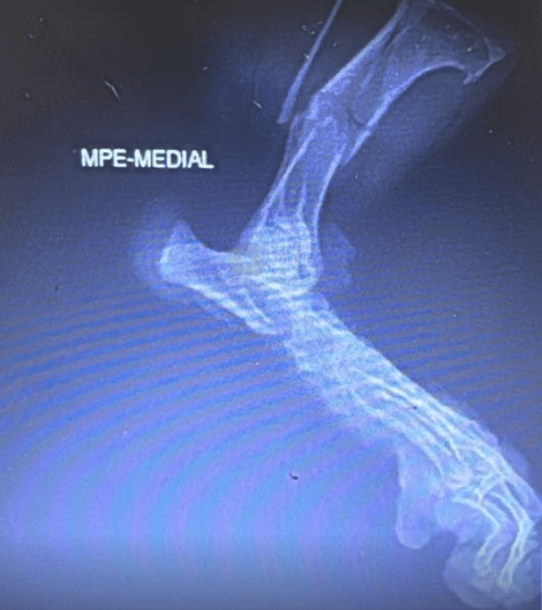

Uma tutora denunciou um ataque sofrido por sua cadela na Praia da Armação, em Penha, e pede ajuda para identificar os responsáveis pelos animais envolvidos. O caso ocorreu no dia 26 de dezembro e resultou em ferimentos graves no animal, que precisou passar por cirurgia.

“Queria relatar um ocorrido com nossa cachorrinha na Praia da Armação. Estávamos com ela na praia e, ao ir embora, uns cachorros da raça poodle escaparam da guia e a atacaram, quebrando a pata dela. Minha cachorra é uma salsichinha pequena, super dócil. Os rapazes que estavam com os cachorros eram dois, com cinco poodles. Temos casa em Penha há mais de 30 anos e frequentamos a praia, isso nunca aconteceu e nunca tínhamos visto algo assim. Queria expor aqui a nossa história para ver se alguém que viu conhece os rapazes, pois nossa pequena Cacau precisou de cirurgia e tivemos vários gastos por causa da irresponsabilidade deles. Primeiro, por que levar tantos cachorros ao mesmo tempo se não conseguem cuidar? Segundo, já imaginou se atacam uma criança ou uma pessoa idosa? Fica aqui minha indignação. Temos imagens da cachorrinha machucada e laudo da clínica veterinária que atendeu ela”, relatou a tutora ao Penha Online.